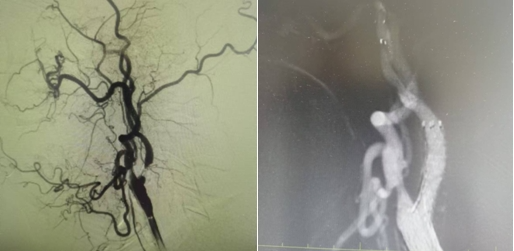

家屬同意后,神經(jīng)介入科團隊迅速給予行腦血管造影,結(jié)果提示:右側(cè)椎動脈重度狹窄。朱洪波副主任表示:該處一旦發(fā)生循環(huán)梗死,輕則癱瘓在床、重則昏迷不醒甚至危及生命,建議盡快對重度狹窄血管積極處理。家屬對患者病情及治療方案詳細了解后,決定接受介入手術(shù)治療。

手術(shù)在局麻下施行,通過經(jīng)橈動脈入路,予以行右側(cè)椎動脈起始處重度狹窄球囊擴張術(shù),經(jīng)股動脈穿刺,微導絲送入球囊至病變狹窄部位進行擴張,擴張后造影提示狹窄部位擴張滿意,基底動脈血流明顯改善,手術(shù)順利結(jié)束。術(shù)后陳大叔上述癥狀完全恢復,大叔妻子感激地說:“感謝國文醫(yī)院的積極救治,來的時候老陳都暈的無法走路,現(xiàn)在都能自己行走了,太感謝了!

1個月前姜大爺(化名)反復出現(xiàn)右側(cè)肢體抽搐癥狀,碾轉(zhuǎn)當?shù)囟嗉裔t(yī)院治療,效果不理想,嚴重影響日常生活,在家人的陪同下來到國文醫(yī)院神經(jīng)介入科。入院后給予行頭MRI彌散+頸部MRA提示:左側(cè)大腦半球分水嶺性腦梗死,左側(cè)頸內(nèi)動脈起始處重度狹窄,給予行DSA提示:左側(cè)頸內(nèi)動脈起始處重度狹窄至閉塞前改變。

丁金明主任指出:患者反復抽搐原來是血管狹窄惹得禍,跟患者家屬交代病情后,患者家屬要求血管內(nèi)介入治療,在導管室傾力配合下,順利完成“左側(cè)頸內(nèi)動脈起始處重度狹窄支架植入術(shù)”,術(shù)后患者未再出現(xiàn)抽搐癥狀,術(shù)后在醫(yī)護人員的精心治療和悉心護理下,患者恢復良好即將出院。